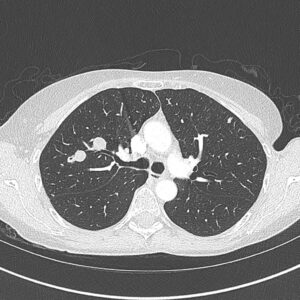

在TPCE中,常规在透视下经股动脉置入5 French (Fr)血管内鞘和5Fr猎头导管,直至到达肺动脉和随后的肿瘤供血肺段分支。可选择放置球囊导管(直径达7mm)以获得更好的结果【Vogl, TJ,2007】这种选择性肺动脉插管导致肿瘤组织的动脉供应受阻,导致靶肿瘤组织的区域性缺血坏死,同时减少对周围正常肺实质的损伤。此后,丝裂霉素和吉西他滨作为化疗药物与碘油和微球栓塞联合应用。因此这延长了注射的细胞抑制物在肿瘤中的储存时间,减少了流入循环系统的流量【Vogl TJ, 2019】,全身性效应的频率和严重程度有限。其他封堵材料有弹簧圈、聚乙烯醇、可降解淀粉微球和明胶海绵。

本研究共纳入223例患者(女138例,男85例;平均年龄(59.3±11.9)岁)。1990年1月至2021年5月期间,对不可切除的肺转移瘤和/或全身化疗无效的患者进行了重复的TPCE,平均治疗次数(4.7±3.7)次。患者以肺转移为主,且多为双肺受累。原发灶为结直肠癌139例,乳腺癌84例。肿瘤供血血管选择性置管,局部应用化疗药,联合碘油和微球。根据修订的RECIST标准评估缓解情况。